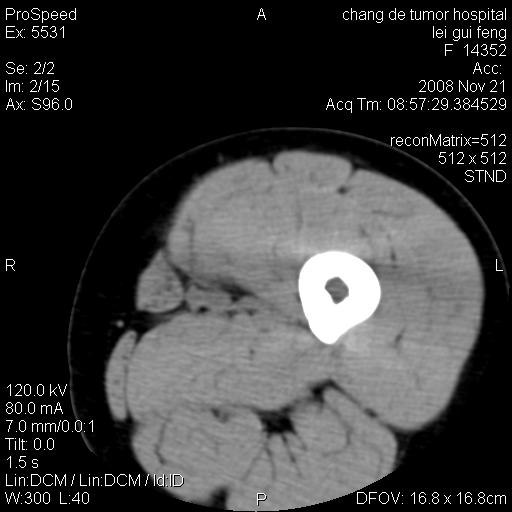

标题: CT16807:女 41 无不适 [打印本页]

标题: CT16807:女 41 无不适

双是软组织肿瘤,病灶内多发钙化,另可见多量脂肪密度影,考虑畸胎瘤,血管瘤,不除外其他